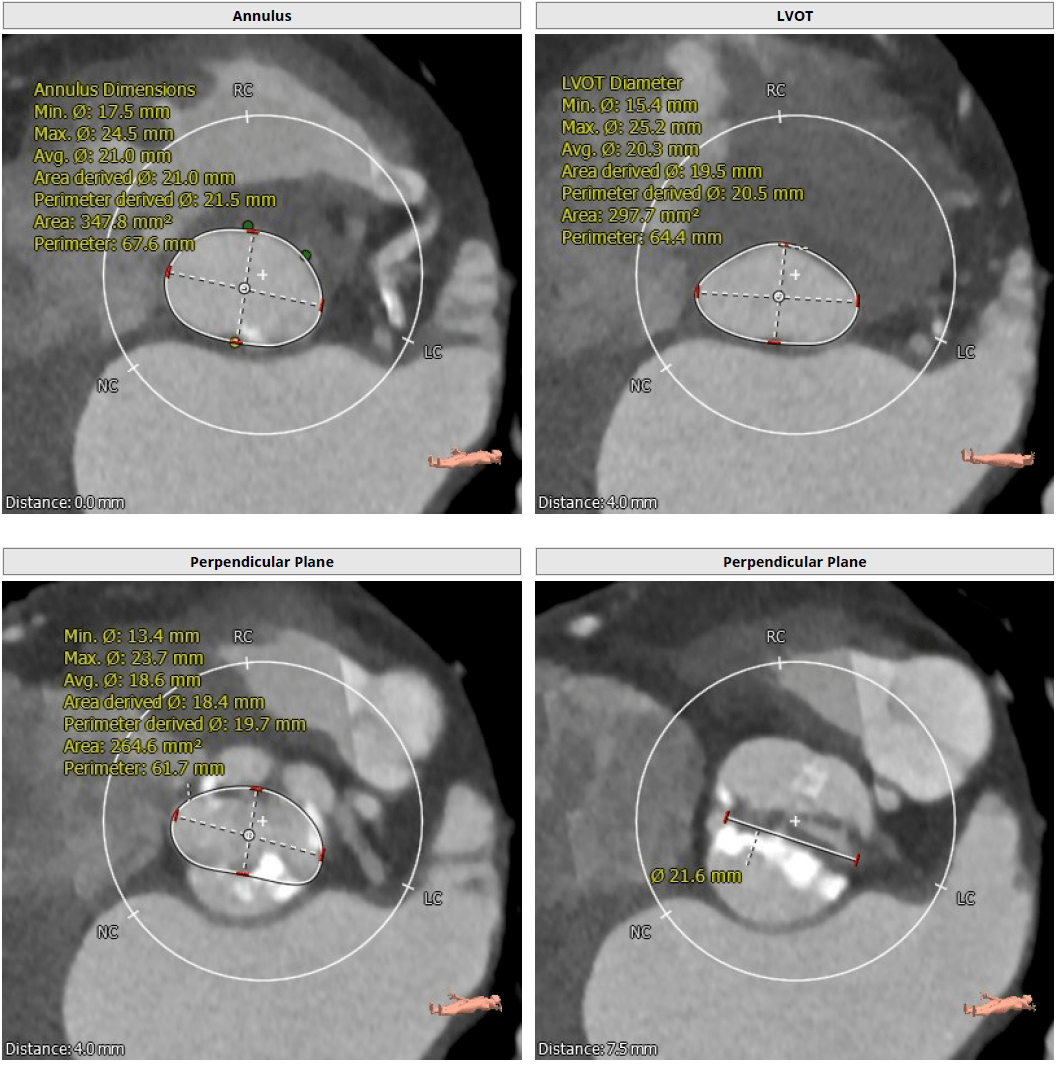

>>主动脉根部解剖: 三叶瓣,中度钙化,窦部结构尚可,冠状动脉高度尚可

1型二叶瓣,左右冠瓣融合,中度钙化,钙化集中在无冠窦侧,主动脉瓣瓣环